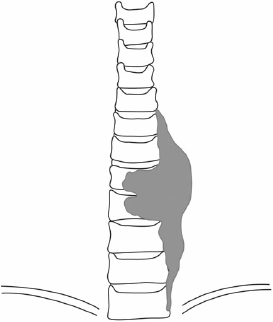

Cancer of the Spine

Cancer of the spine, both secondary and primary, are of particular interest to this practice. Dr Mobbs has undertaken further training in complex spine cancer surgery and reconstruction.

Click on the thumbnails for enlarged view